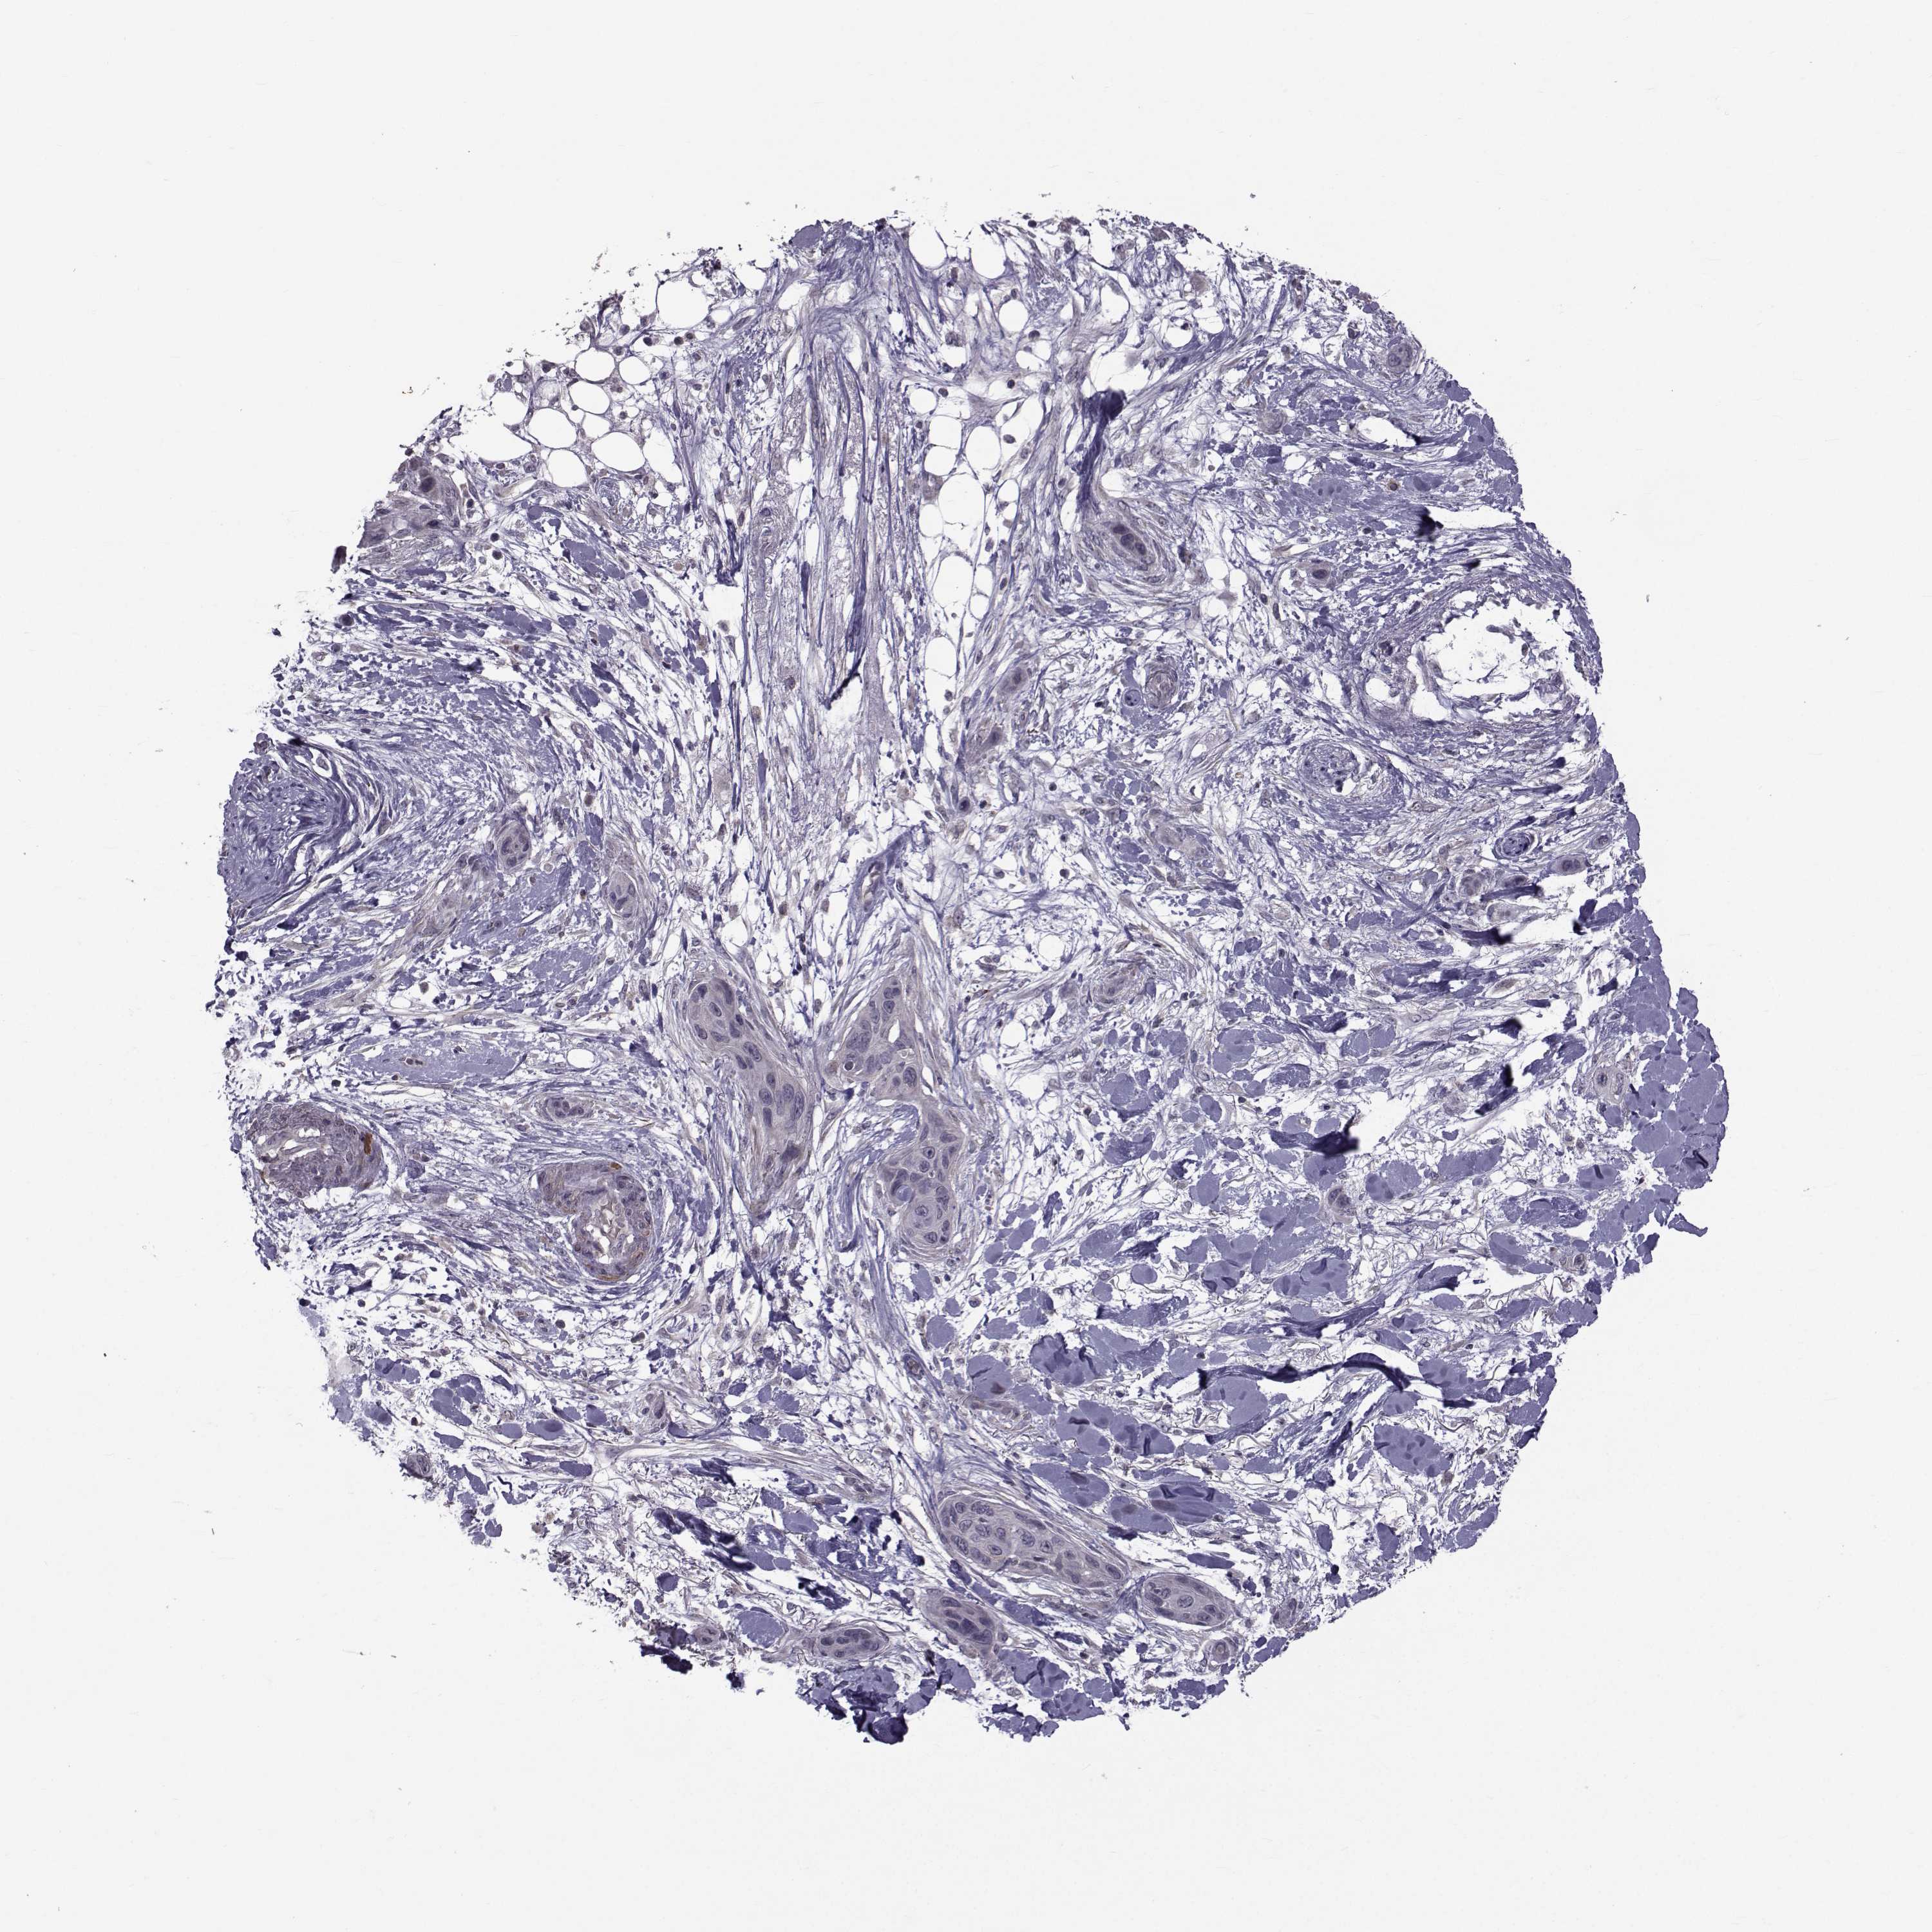

CANCER SKIN CANCER Show tissue menu

SKIN CANCER - Protein expressioni

A mouse-over function shows sample information and annotation data. Click on an image to view it in a full screen mode. Samples can be filtered based on level of antibody staining by selecting one or several of the following categories: high, medium, low and not detected. The assay and annotation is described here.

Each image is clickable and will lead to virtual microscopy that enables deeper exploration of all samples and also displays staining intensity scores, fraction scores and subcellular localization as well as patient and tissue information for each sample.

Antibody HPA044393

Squamous cell carcinoma, NOS

Basal cell carcinoma